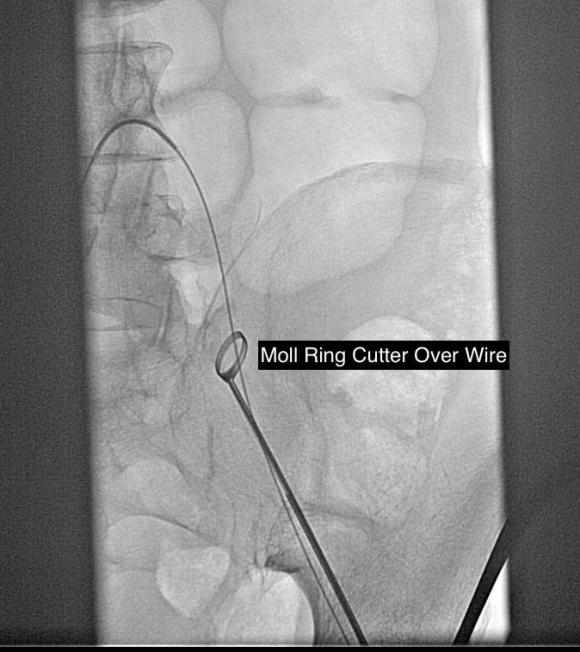

The common femoral endarterectomy is done from its distal most point and the Vollmer ring is used to mobilize the plaque. A Moll Ring Cutter (LeMaitre Vascular) is then used to cut the plaque.

Remote endarterectomy is a bit of a lost art from the early days of vascular surgery. A ring dissector (Vollmer Ring Dissector, LeMaitre Vascular) is used to liberate the plaque from the remnant adventia. A cutting device (Moll Ring Cutter, LeMaitre Vascular) shown third from left below is used to divide the plaque.

The common femoral artery plaque is usually contiguous with plaque in the external iliac artery and surgeons who perform a lot of CFA endarterectomy have various maneuvers to remove as much plaque as possible, up to stenting the end point of the plaque down to the endarterectomy patch. I have never been satisfied with this because the EIA behaves differenty than the CIA (am looking into this!) in my experience and placing stents even minimally across the inguinal ligament is not desirable. Sending the dissector up to the EIA origin frees the plaque to be removed completely with the CFA plaque. The clip below shows the Vollmer Ring dissecting plaque up to the EIA origin. I do this over a wire in the pelvis because in the rare instance of leak or rupture, rapid control is possible without having to open the abdomen.

Once freed, the cutter is used to transect the plaque and the end point is tacked down with a stent at the distal common iliac/EIA origin which is a better place for a stent than the inguinal ligament.

The right EIA plaque was mobilized with a Vollmer ring dissector, and cut with a Moll ring cutter (LeMaitre).